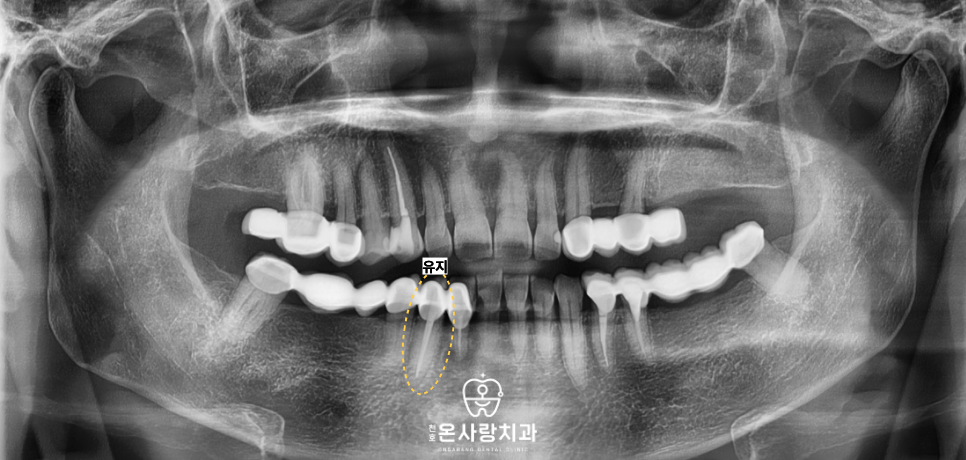

브릿지의 다른 기둥이었던

작은어금니와 큰어금니의 경우에는

보철물을 제거하고 보니

이차 충치가 진행되어 있었습니다.

보철물 내부에서 충치가 발생하면

환자 스스로가 이를 인지하기 매우 어렵습니다.

이에 따라 오염된 부위를 깨끗하게 제거하고

신경치료를 병행하여 치아의 수명을 연장한 뒤

크라운을 씌워 개별적으로 보호하였습니다.

반면 송곳니 치아는 뿌리와

전반적인 치질 상태가

양호한 것으로 판단되었습니다.

따라서 해당 치아는 무리하게

발치하지 않고 크라운 보철물을

새롭게 제작하여 씌워줌으로써

본래의 기능을 유지하도록 하였습니다.